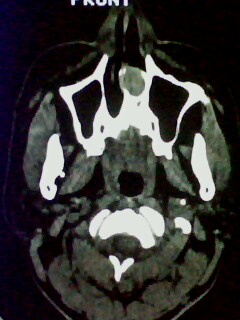

以下是引用随光逐影在2009-5-20 19:22:00的发言:[br]1)考虑左上颌骨近中线区含牙囊肿。2)鼻中隔右突偏曲。3)双侧下鼻甲肥大。